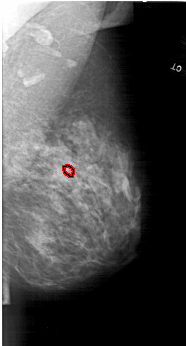

A_1664_1.RIGHT_MLO

RIGHT_MLO LINES 6226 PIXELS_PER_LINE 3346 BITS_PER_PIXEL 12 RESOLUTION 43.5 OVERLAY

FILE: A_1664_1.RIGHT_MLO.OVERLAY

TOTAL_ABNORMALITIES 1

ABNORMALITY 1

LESION_TYPE CALCIFICATION TYPE PLEOMORPHIC DISTRIBUTION LINEAR

ASSESSMENT 4

SUBTLETY 2

PATHOLOGY MALIGNANT

TOTAL_OUTLINES 1

BOUNDARY